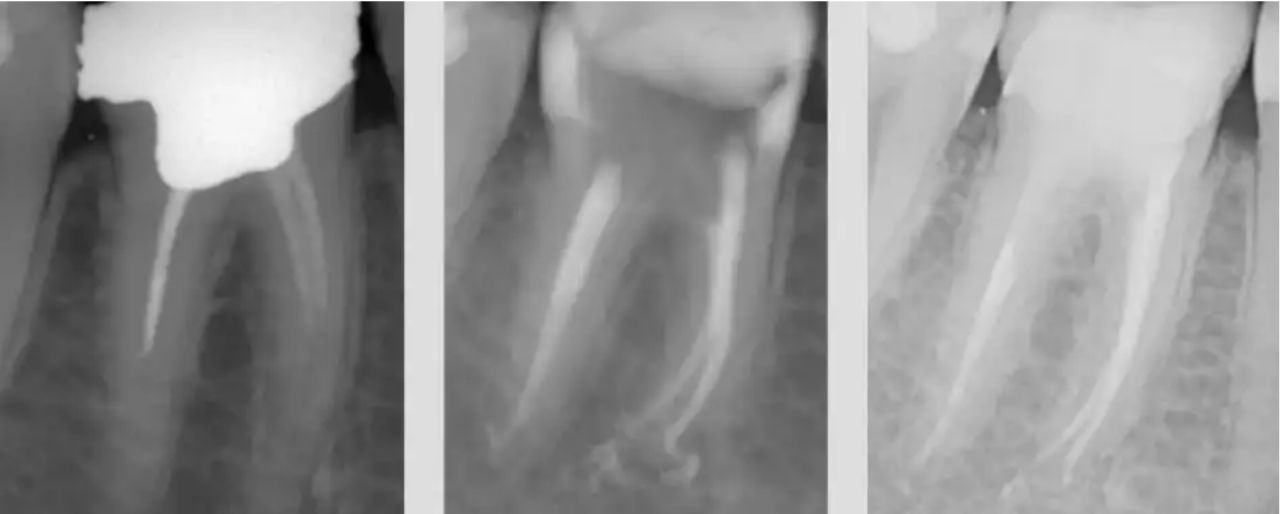

Обратитесь к стоматологу для рентгеновского снимка, чтобы определить точное расположение излишков пломбировочного материала.

Почему гуттаперча выходит за верхушку? Часть 1

Осложнения при лечении пульпита. Попадание пломбировочного материала за пределы корня зуба

Какой силер лучше? Выход силера за верхушку. Силер в стоматологии